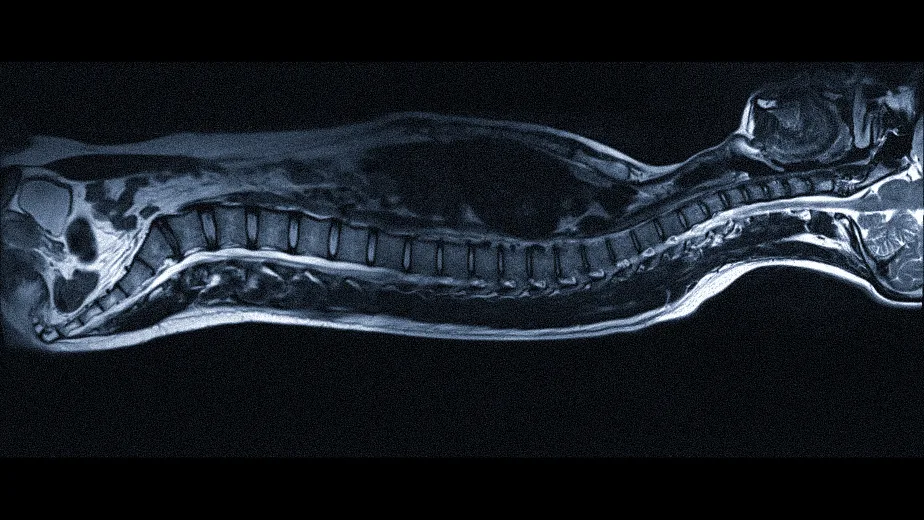

Магнитно-резонансная томография позвоночника является одним из наиболее информативных методов диагностики, позволяющим получить детальное изображение состояния костных структур, межпозвоночных дисков, нервных окончаний и мягких тканей. Этот метод помогает врачам точно определить причину болей и других неприятных симптомов, а пациентам — своевременно начать лечение и избежать осложнений.

Во время процедуры создается серия детальных снимков, которые позволяют рассмотреть позвоночник в разных плоскостях. Это дает возможность выявить даже минимальные изменения в тканях, которые могут быть причиной боли или дискомфорта.

Исследование охватывает различные отделы позвоночника: шейный, грудной и поясничный. Каждый из них выполняет важные функции, и нарушение их работы может существенно повлиять на общее состояние здоровья.